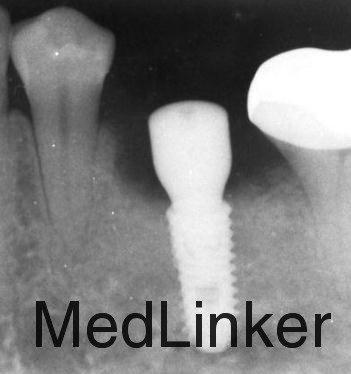

专科检查:下颌乳Ⅴ滞留,松动Ⅲ度。x线片检查:35先天缺失。下颌乳Ⅴ牙根吸收到牙颈部。

处理:(1)拔除下颌乳Ⅴ。(2)一个月后行种植修复。

本病例即刻种植也可以,但考虑软组织的情况,建议一个月后软组织愈合后种植,愈合基台周围的软组织封闭要比即刻种植要好。